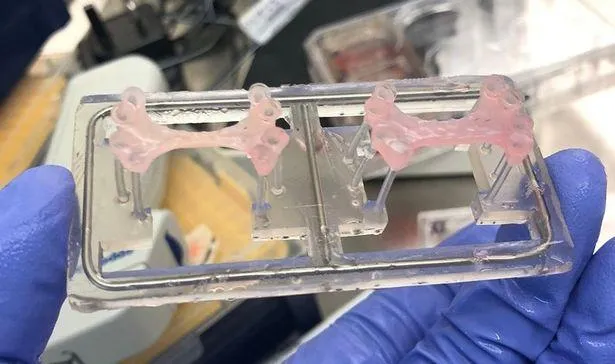

Ученые из Имперского колледжа Лондона вырастили в лабораторных условиях пластырь размером 3 на 2 сантиметра, пишет MedicalExpress.

Пластырь содержит до 50 миллионов человеческих стволовых клеток, которые превращаются в здоровую сердечную мышцу. Разработка содержит вещества, которые способны восстанавливать и обновлять клетки сердца.

Пластырь содержит до 50 миллионов человеческих стволовых клеток

Эксперты уже провели исследование над кроликами. Исследования показали, что пластырь улучшает функцию сердца после сердечного приступа. После окончания периода до 4 недель детальные сканирования сердца показали, что левый желудочек сердца (камера, отвечающая за перекачивание крови к телу через аорту) восстанавливается без развития аномальных сердечных ритмов.

По словам исследователей, пластыри подпитывались кровеносными сосудами, которые растут от сердца реципиента.

Пластырь, восстанавливающий сердце после приступа

Ученые будут проводить дальнейшие исследования для разработки клинических испытаний: сначала для проверки безопасности, затем – для того, чтобы увидеть, можно ли достичь подобных уровней восстановления сердца у людей.